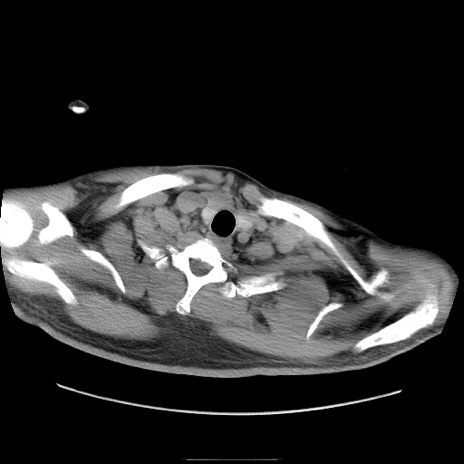

症例22(横断像)

【症例】50歳代男性

【主訴】腹痛

【現病歴】AVMからの被殻出血のため回復期リハ病棟入院中。 本日午後3時頃急に下腹部痛が出現した。

【既往歴】AVM、被殻出血、虫垂炎、高血圧

【身体所見】意識晴明、左半身不全麻痺、会話の理解は良好、36.5°C、腹部:膨隆、全体に板状硬、下腹部正中に圧痛点あり、反跳痛-、筋性防御不明、右下腹部にope scar

【データ】WBC 9400、CRP 0.06